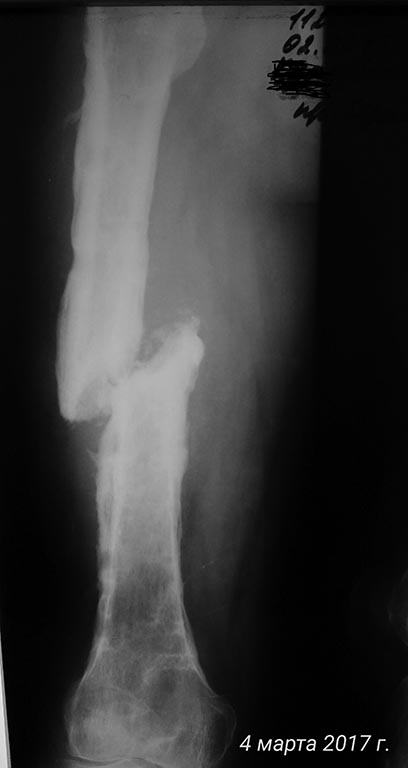

Дополняю рентген архив

Прокомментирую:

самый первый снимок от 12.2016

Последние от 02.2017.

По рентгенограммам - тотальный остеомиелит бедренной кости. Для подтверждения можно сделать спиральную КТ. В Советское время выполнялись трепанации кости, долговременные активные промывные системы, эндостальное облучение кости лазером и т. п. Длительный постельный режим, огромный расход биологически активных препаратов, непрерывный врачебный уход... И это только для санации очага. Если нет возможности тотального эндопротезирования, то ампутация. И, так - делают!

Да,не сросся,судя по более свежим снимкам. Тогда промывная система после секвестрэктомии недели на 2 и иммобилизация вытяжением,с переводом в коксит месяца через 1,5-2 + все вышеперечисленное... О синтезе даже нет речи пока..